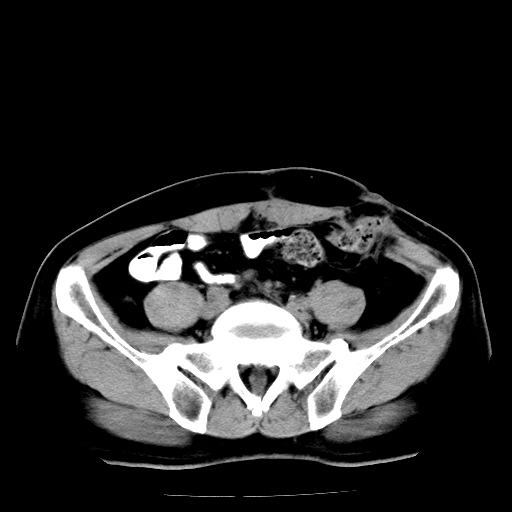

男,66岁,直肠癌术后一个月,化疗前ct检查。

直肠癌造瘘术后改变,周围淋巴结转移

前列腺肥大

直肠癌造瘘术后改变,盆腔多发淋巴结转移

直肠癌造瘘术后改变,直肠周围软组织增厚,盆腔多发淋巴结转移。前列腺肥大。